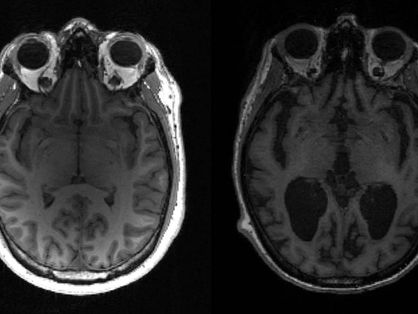

Legenda: Estudo identifica sinais que podem prever diagnóstico de Alzheimer

Um estudo da Universidade de Cambridge, no Reino Unido, revelou que é possível detectar sinais precoces de demência até nove anos antes de o paciente receber um diagnóstico específico, como Alzheimer.

A análise das informações reunidas no banco de dados biomédicos revelou que pessoas que desenvolveram Alzheimer já apresentavam um desempenho pior do que indivíduos saudáveis em tarefas de resolução de problemas, tempo de reação a estímulos, capacidade de lembrar de números e memória prospectiva, entre outros. Isso também foi constatado em pessoas que desenvolveram uma forma rara de demência chamada de demência frontotemporal.